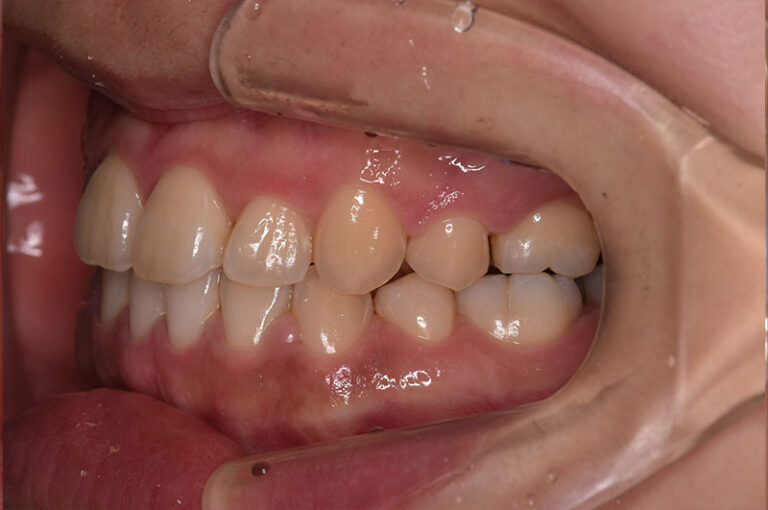

今回は反対咬合に対して、外科手術を行わずに矯正治療のみで改善した成人の症例をご紹介します。

「反対咬合=手術が必要」と思われがちですが、噛み合わせの状態によっては、今回のように矯正治療だけで改善が可能なケースもあります。

治療前後の変化を実際の症例写真でご覧いただくことで、

反対咬合がどのように改善するのかを、イメージしていただければと思います。

症例の概要(手術なし・成人の反対咬合)

術前

術後

| 主訴 | 反対咬合 |

| 初診時年齢 | 24歳 |

| 治療内容・使用した装置 | 頬側ブラケットを用いた永久歯全体の矯正治療、アンカースクリュー |

| 抜歯の有無 | 左右下顎第一小臼歯、左側上顎第二小臼歯抜歯 |

| 治療期間 | 約24ヶ月 |

| 費用 | 総額819,500円(税込) (相談料、検査料、診断料、動的治療費、抜歯費、アンカースクリュー埋入、除去費、保定期間料等含む) |

| 治療に伴うリスク・副作用 | 歯の移動に伴う痛み、上下顎前部の歯根吸収、装置による口内炎、ブラッシング不良によるむし歯、歯周炎 |